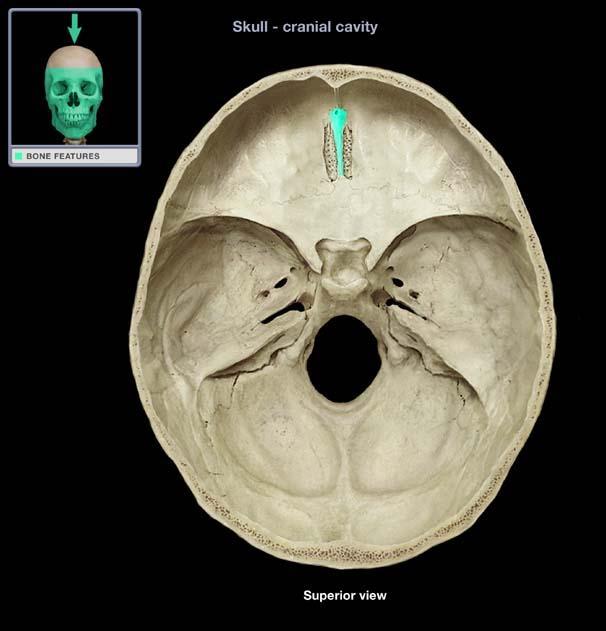

Occipital Bone Features

Foramen Magnum, Occipital Condyle, External Occipital Protuberance

Foramen Magnum

Occipital Condyle

External Occipital Tuberance